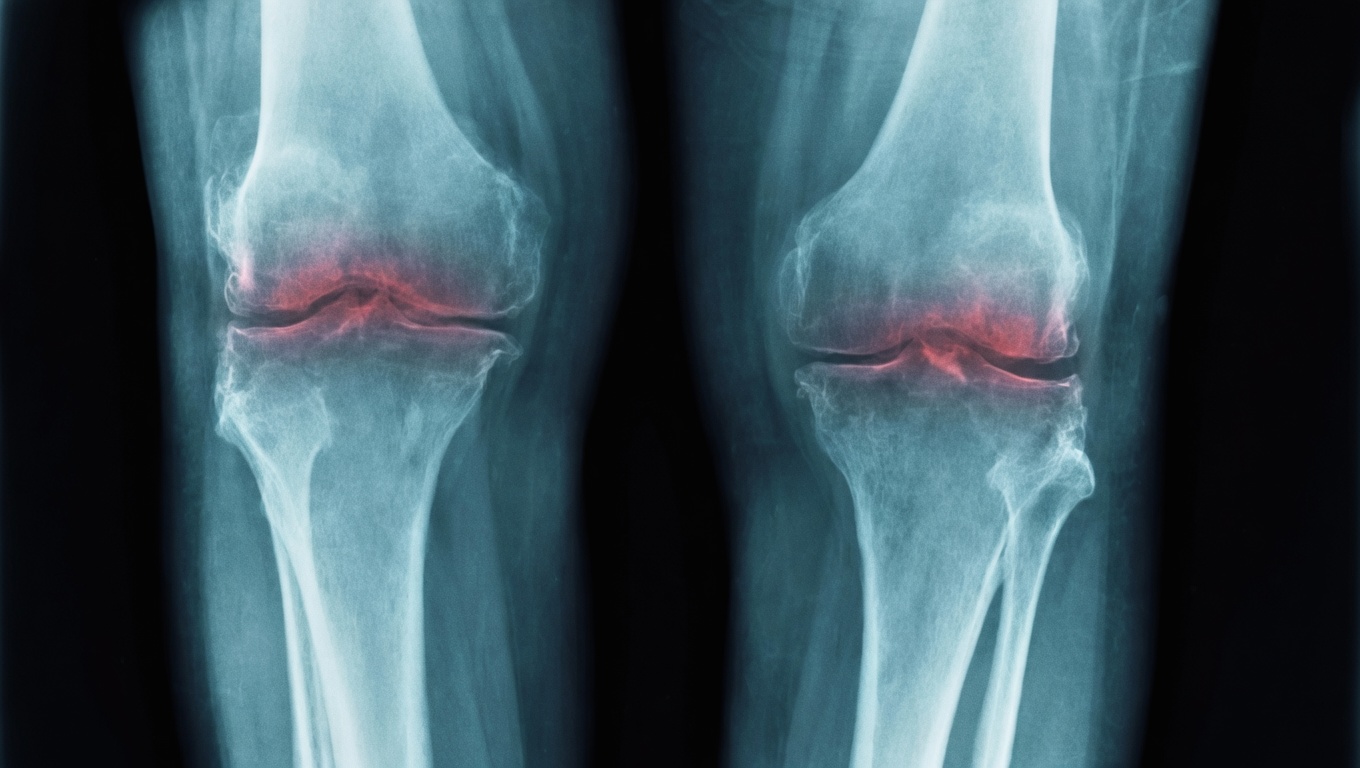

Nelle articolazioni degli anziani, la cartilagine si assottiglia perché una singola proteina, la 15-PGDH, diventa sempre più abbondante con l'età e ostacola le molecole che riparano i tessuti e smorzano l'infiammazione. Partendo da questa osservazione, un gruppo della Stanford University guidato dalla microbiologa Helen Blau ha verificato se bloccare quella proteina potesse invertire l'usura del ginocchio nei topi. I risultati, pubblicati su Science nel novembre 2025, suggeriscono che la risposta sia positiva.

Nei topi anziani con cartilagine già consumata, la somministrazione di un inibitore della 15-PGDH ha portato a un ispessimento misurabile del tessuto articolare del ginocchio. In topi giovani sottoposti a una lesione simile alla rottura del legamento crociato anteriore, lo stesso inibitore ha impedito lo sviluppo dell'osteoartrite che normalmente seguirebbe un trauma di quel tipo. Gli animali trattati camminavano con andatura più stabile e caricavano di nuovo peso sulla gamba infortunata, indizi indiretti di una riduzione del dolore.